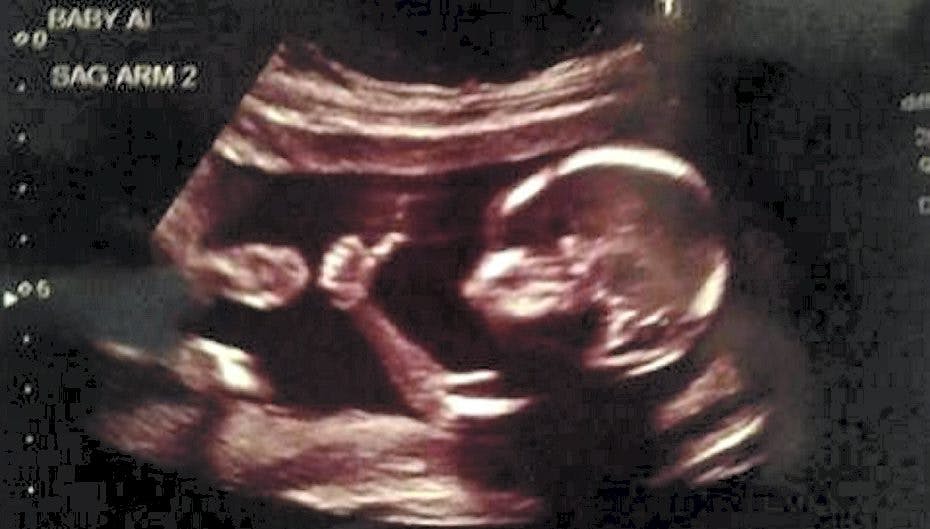

Billede går verden rundt: Ufødt barn giver thumbs up

Ikke engang født, men allerede i stand til at give thumbs up

Den lille baby er ikke engang født, men har ingen problemer med at udtrykke sig (Foto: Brandon Hopkins/Facebook)

For det lille ufødte barn giver et vaskeægte thumbs up til verden uden for.

Den kommende far, 31-årige Brandon Hopkins, lagde billedet af sin ufødte søn/datter på internettet 28. august - og det sjove billede gik hurtigt verden rundt.